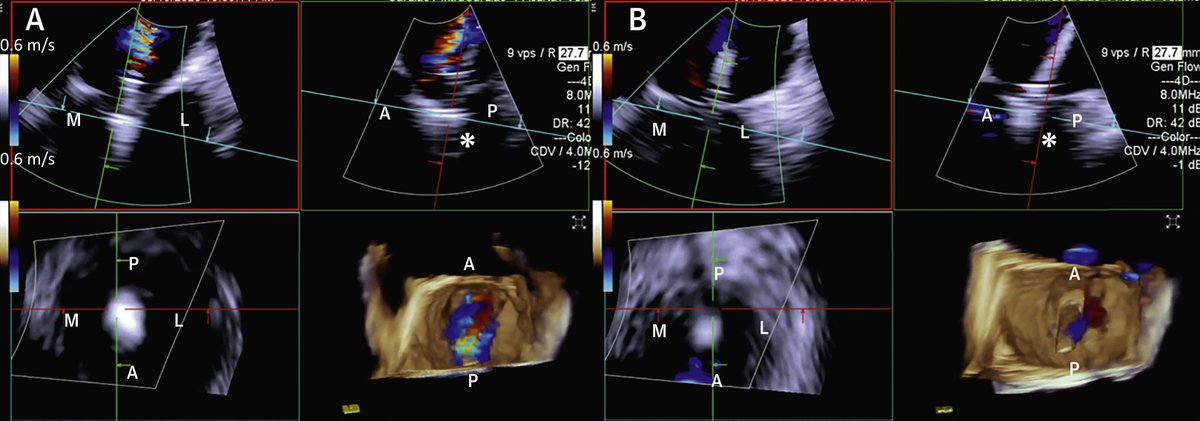

VeriSight Pro guided MitralClip. X-Plane, MPRs, 3D+Transilumination, Omniplane, important features of any 3D ICE catheter to have for SHD interventions. #3DICE @GilbertTangMD @StevenYakubov

Finally out in print! @SiemensHealth 4D ICE in #Mitraclip #TEER @JACCJournals #JACCImg. Great collaboration with @caresans26 @StevenYakubov #GaganSingh #JasonRogers

While TEE = gold standard for intraprocedural guidance of #MitraClip transcatheter mitral edge-to-edge repair, 4D intracardiac echo (ICE) w/ conscious sedation = feasible alternative if TEE contraindicated. https://t.co/SO8BqfPFnY

just online! @JACCJournals #JACCImg 4D ICE guidance in #MitraClip in pts who can’t get TEE. Great collaboration @caresans26 @StevenYakubov @JasonHRogersMD GaganSingh https://t.co/T5lqMoyRYZ